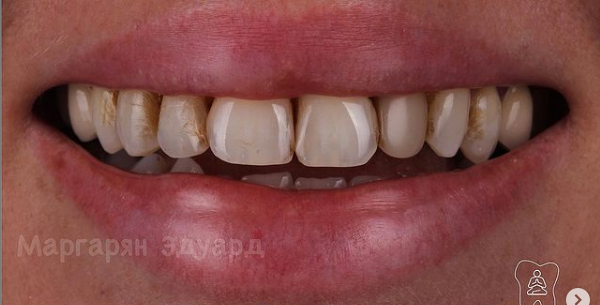

12 работ в портфолио

Маргарян Эдуард Вадимович принимает в МЕДИЦИНСКОМ СТОМАТОЛОГИЧЕСКОМ ЦЕНТРЕ НА ЗЕЛЕНОГРАДСКОЙ в Москве. Стаж 13 лет. Специализируется на ортопедии. Имеет 12 работ до/после в портфолио. Для уточнения дополнительной информации о специалисте или записи на прием можно позвонить по телефону

Установка керамических виниров

Установка виниров E-max